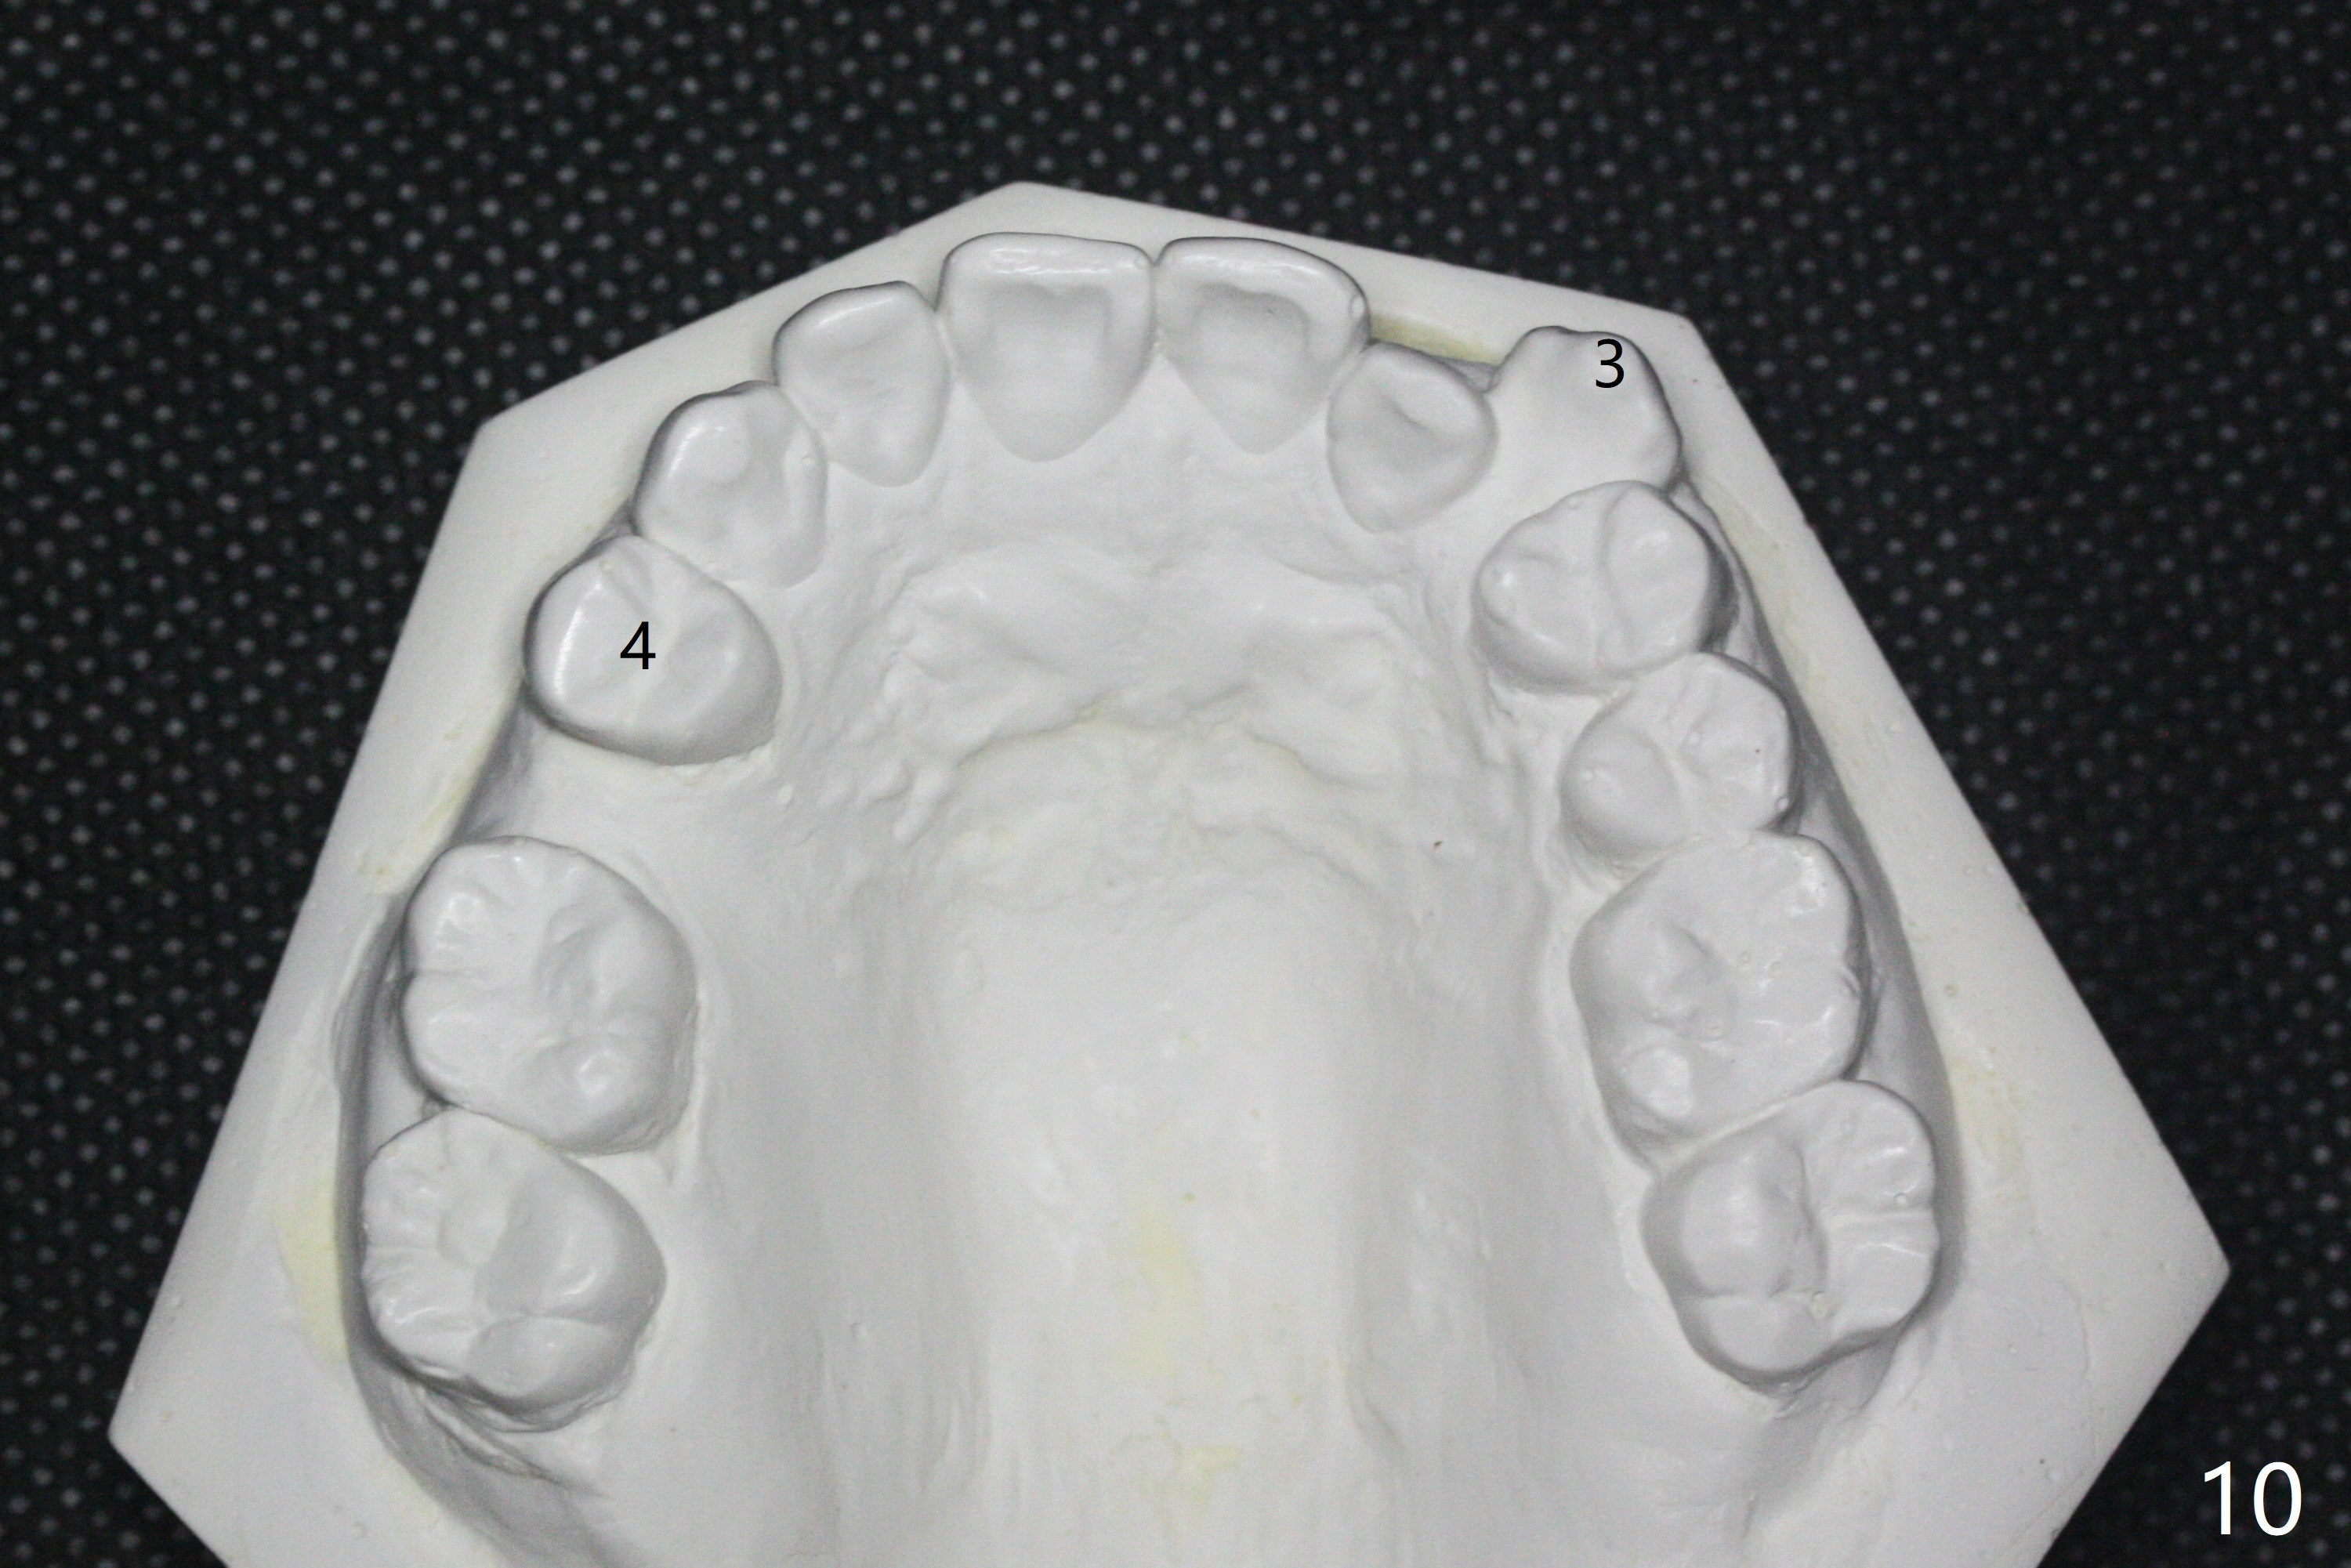

A 40-year-old man requests orthodontics after #17 and 32 extraction. UL5 is missing (Fig.1), while the upper midline deviates to the left (Fig.2 arrow) with crowding between UL2 and 3 (Fig.3). The main goal is to retract UL5 distal and move the upper midline to the right to alleviate UL anterior crowding. Implant will be not needed. To monitor potential root resorption associated with tooth movement, preop PAs are taken (Fig.4-7). The space for an implant at UR5 is narrow. UR4 needs to be distalized using UR7 or a miniimplant distal to UR7 as an anchor (Fig.8). UR4 and 3 will be repositioned to establish Class I occlusion (Fig.9). The space gained by UR4 distalization may be enough to correct the upper midline deviation and UL3 malposition (Fig.10). Brackets will be placed in the lower arch in spite of the normal alignment (Fig.11). UL2 and 3 brackets are unable to be engaged to 14 niti wire (Fig.12). Next visit try to engage UL2 bracket. If not, save the old wire for possible future reuse. Closed spring is placed with 18 ss wire <3 months post banding (coronavirus). Three weeks post closed spring between UR4-7, UR3,4 are being distalized (Fig.13). Distalization of UR4 is not much in 5.5 months (Fig.14,15). It seems necessary to use a miniimplant distal to UR7 as an anchor (Fig.16 white circle), place a long hook mesial to UL4 (more or less root movement instead of tilt) and place the same closed spring between the anchor and hook. In spite of the fact that UR4 seems to have been completely distalized and that UR2 is being distalized 8 months post banding (Fig.18), a 8 mm long mini-implant is placed in the maxillary tuberosity with minimal local anesthetic (Fig.17,19). A longer closed spring (18 mm) is placed between the implant and UR3 hook (Fig.20). Next appointment a lingual button will be placed at UR4 for rotation, while a post hook mesial to UR3 for torque. UR3 distalizes with the help of UR mini-implant, which is unfortunately loose. Next visit place lingual button at UR4 (Fig.21 arrow) to distalize the lingual cusp. Crimpable power hook is placed mesial to UR2 for distalization (for root torque, Fig.22). If it works, remove the wire and reposition the hook for UR1 next visit. UR2 is distalized in one appointment (~ 1 month, Fig.23, as compared to Fig.22). With lingual button at UR4, rotation seems to have been corrected shortly (Fig.24 arrow).